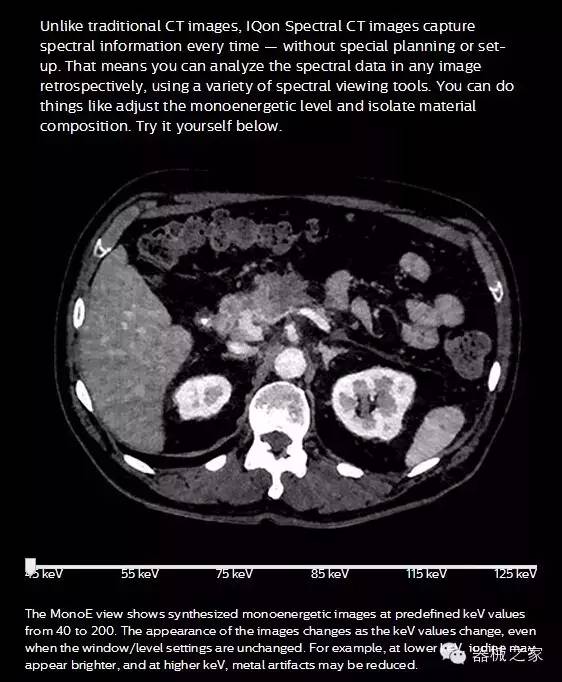

IQon光譜CT能夠按照需求提供光譜量化和工具,并能通過簡單工作流程、在低劑量下對結(jié)構(gòu)進(jìn)行定性分析

IQon光譜CT -- 是業(yè)界首臺以探測器為成像基礎(chǔ)的光譜CT,它可以在單次常規(guī)掃描下獲得傳統(tǒng)解剖影像及光譜功能影像。不僅可以提供精準(zhǔn)的診斷信息,還可簡化工作流程、在低劑量下完成定量與定性分析。